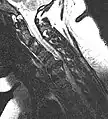

L'imagerie par résonance magnétique peut montrer la hernie, le canal vertébral, les nerfs, les tissus environnants. Les tissus mous sont les mieux analysés par cet examen qui est le plus performant pour le diagnostic de hernie discale. Les images pondérées en T2 montrent clairement la hernie.

IRM cervicale sagittale montrant une hernie discale de niveau C6-C7.